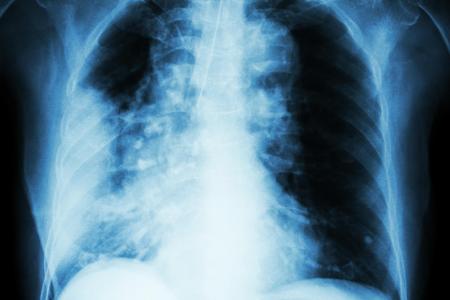

Le service de radio-oncologie des HUG a effectué cet été son premier traitement de radiothérapie pulmonaire en utilisant un navigateur GPS du corps humain.

Utilisée jusqu’ici pour le cancer de la prostate, cette technologie localise la tumeur en temps réel et en continu malgré les mouvements respiratoires. Elle réduit ainsi le volume de tissus sains irradiés et augmente la précision du traitement.

Les émetteurs implantés dans la tumeur à traiter ou à proximité transmettent de manière extrêmement précise ses coordonnées spatiales. L’irradiation est interrompue automatiquement si la tumeur sort de la zone. Elle est réenclenchée dès qu’elle y revient.